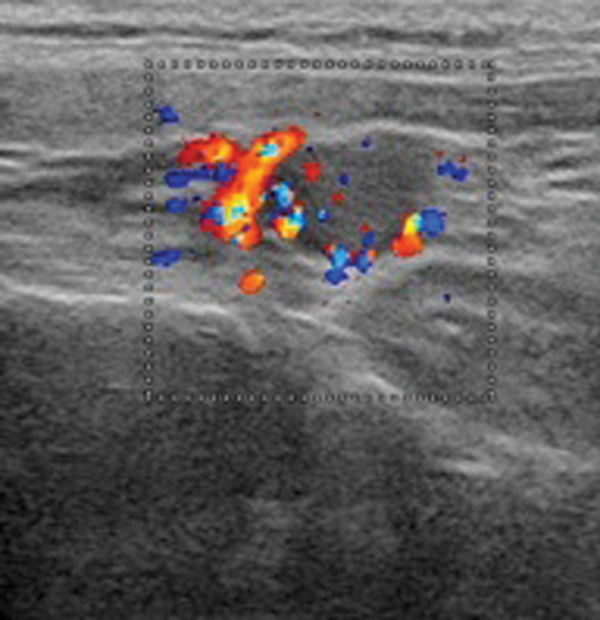

Figure 2: Dual Isotope 123I 99mTc MIBI Scan demonstrating activity on the subtraction images in the left neck consistent with adenoma.

However, relatively long imaging times of up to 20 minutes are required which may result in movement artifacts. More recently, 99mTc-sestamibi has been used in functional parathyroid imaging (Figure 2). This is taken up by both thyroid and by abnormal parathyroid tissue, and the radiopharmaceutical may be used for either subtraction or differential washout techniques with reported sensitivities of 88% for solitary adenomas [6]. Sestamibi subtraction imaging is used in conjunction with either 99mTc-pertechnetate or 123iodine to identify the thyroid gland. Washout methods utilise the differential clearance rate of sestamibi from thyroid and parathyroid tissue - washout from the thyroid is rapid compared to delayed washout in abnormal parathyroid tissue. The technique is simple, relatively quick and only uses one tracer but small or rapidly clearing adenomas may be missed [6].